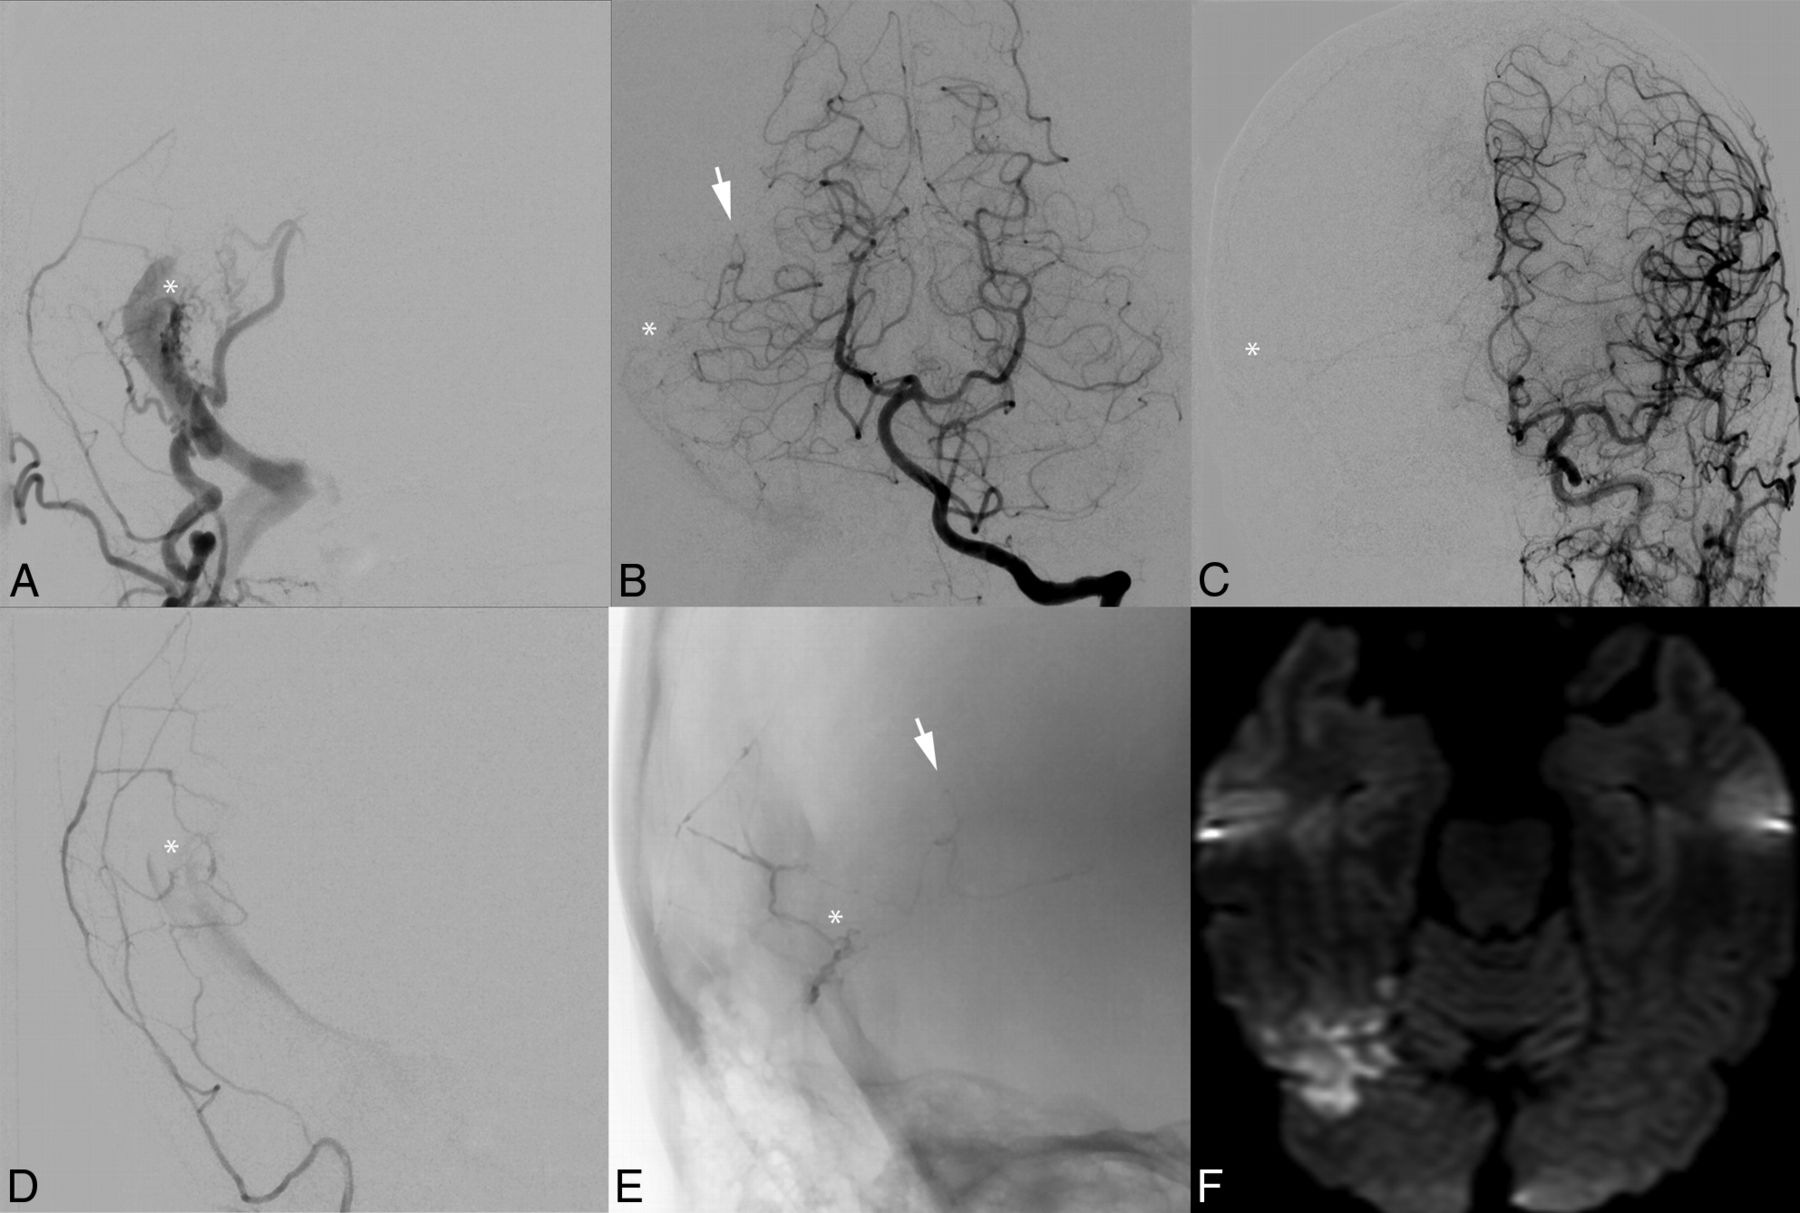

Postoperative parenchymal hemorrhage and possible venous infarction following surgical ligation of a residual DAVF. A middle-aged man had intermittent speech arrest and multiple headaches for several years. Anteroposterior (A) and lateral (B) angiograms demonstrate a variant-type right transverse-sigmoid sinus junction Borden-Shucart grade III DAVF supplied by dural branches of the external carotid artery and pial branches of the MCA (C) with retrograde drainage to the vein of Labbé (D), that anastomotically drains to the vein of Trolard. Following Onyx embolization of the dural external carotid artery branches, only the pial MCA supply to the fistula continued to drain to the cortical vein as demonstrated on early (E), mid (F), and late (G) images from a lateral ICA angiogram. During surgical ligation of the residual DAVF, extensive intraoperative bleeding was noted. A CT performed immediately postoperatively (H) demonstrates right temporal intraparenchymal hemorrhage. The patient did not have a new neurologic deficit postoperatively.

Recently, DAVFs with pial artery supply were shown to result in intraoperative hemorrhage in 33% of patients17—significantly more than in patients with DAVFs without pial artery supply. Although symptomatic intraoperative hemorrhage was not seen in any of our cases (though an asymptomatic hemorrhage is shown in Fig 4), it helps support our assertion that DAVFs with pial artery supply carry a higher operative risk, and treatment should be approached with appropriate caution.